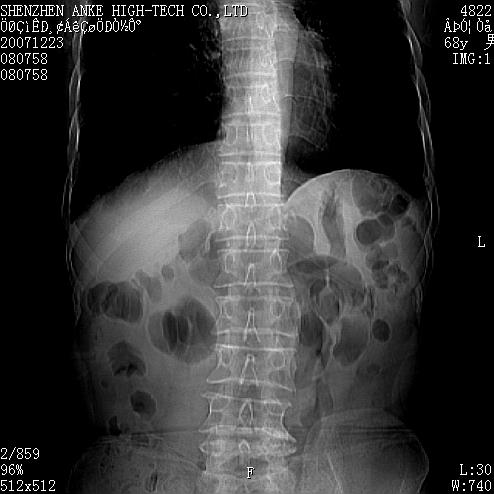

患者:男,63岁,2年前胆囊切除术后,现右上腹部剧烈疼痛近2天.

请看第一张正位片,胸主动脉象有扩张,胸主动脉瘤?